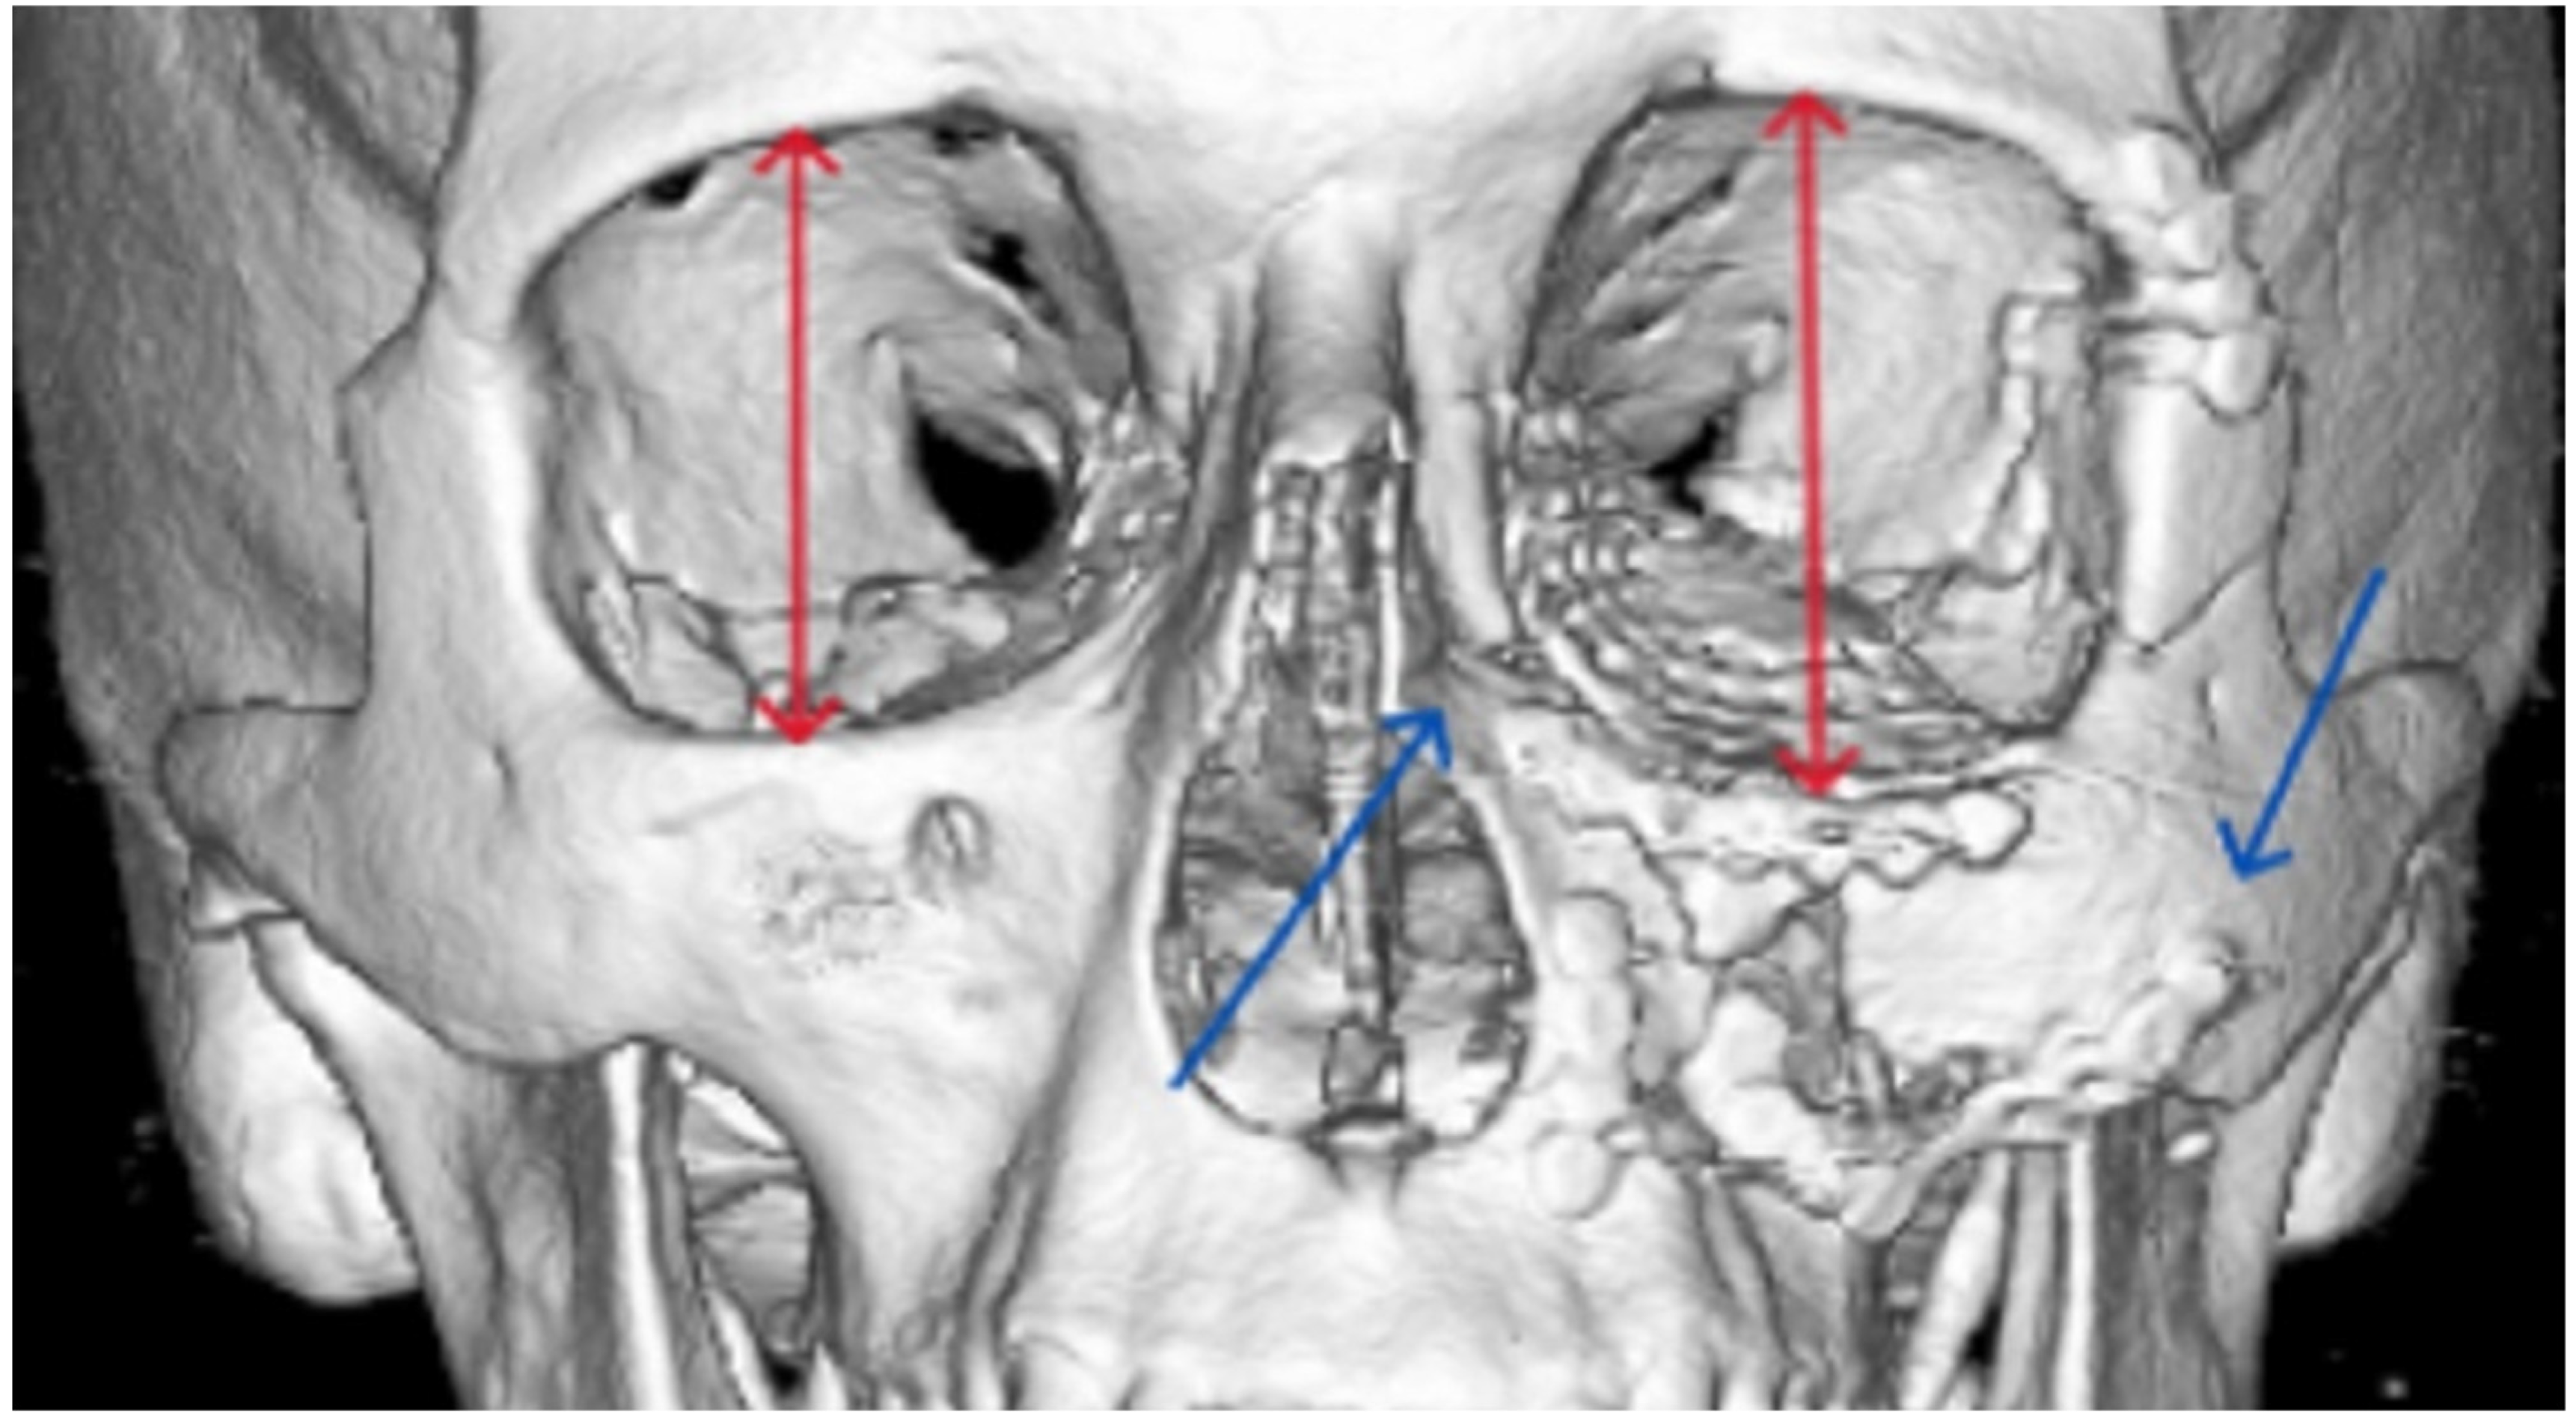

| Midface | 13 | ||||

| Zygomatico–orbital complex * | 6 | 4 | 6 inadequate reductions | ||

| Le Fort ** | 4 | 1 (Le Fort III) | 4 inadequate reductions | ||

| Orbit | 4 | 0 | 3 inadequate reconstructions of orbital floor fractures, 1 orbital deformity due to inadequate reduction of the zygomatic bone | ||